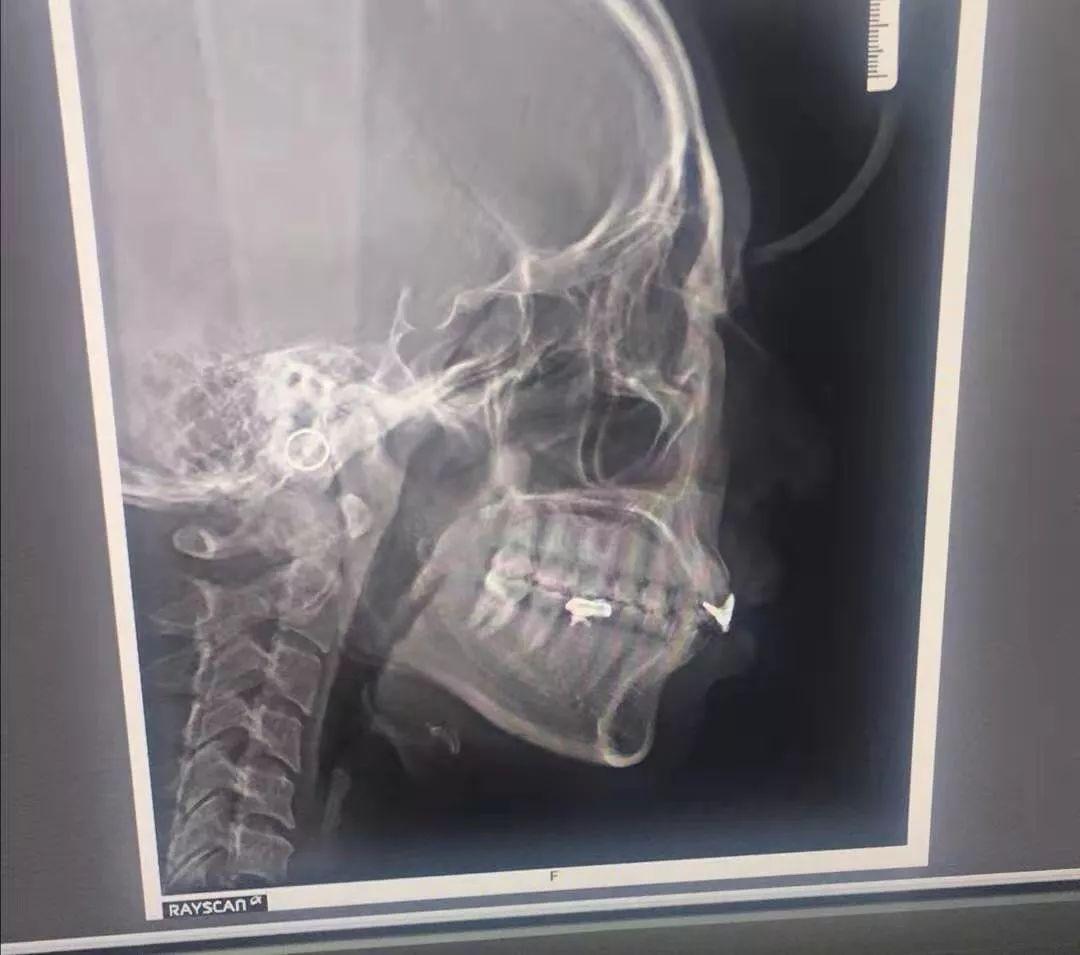

牙齒 X 光片

醫(yī)生說我原本補(bǔ)過牙,不適合傳統(tǒng)牙齒矯正,而且隱形矯正還能幫我矯正牙齦突出的問題。這簡直是天大的好消息!